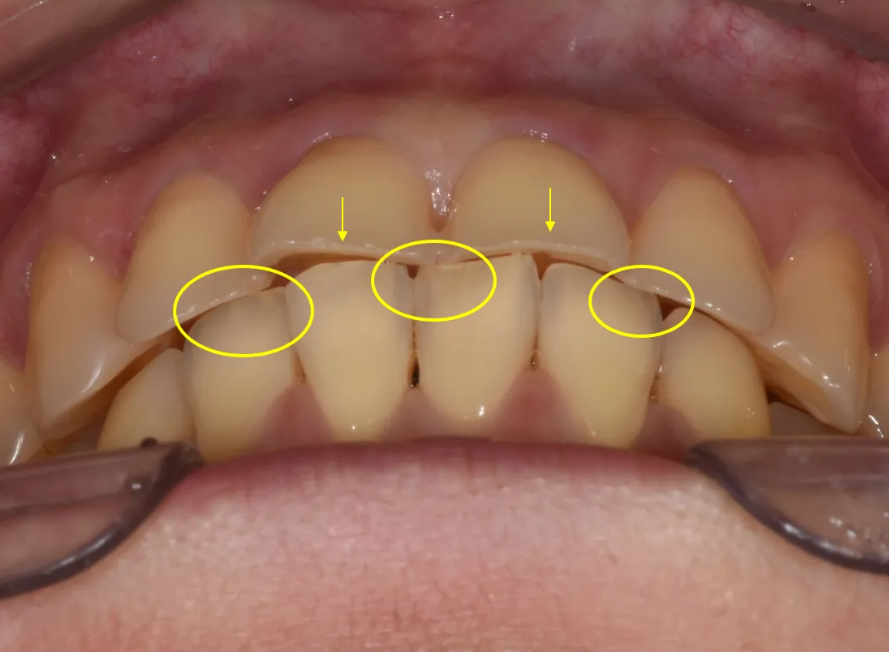

(1) 윗니 안쪽면의 마모 (2)나비이빨 형태 재확인.

윗니 안쪽(혀 쪽) 면을 보면 치아가 상당히 닳아서 치질이 많이 소실된 상태였습니다. 이는 화학적 침식이나 마모에 의한 것으로 추정되며, 이 부분이 이번 치료 계획에서 가장 중요하게 고려해야 할 사항이었습니다.

윗니 클로즈업 – 앞면 레진 수복 흔적, 누런 색상, 잇몸 라인 불균형

가운데 앞니 두 개와 왼쪽 옆 앞니의 잇몸 라인도 불균형하여 비심미적이었고, 가운데 앞니 사이에는 검은 삼각형(Black Triangle)이라 불리는 빈 공간이 보였습니다.